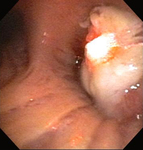

Bronchoscopic therapy for central airway obstruction of the right mainstem: post-mechanical debulking

From the collections of Jose Fernando Santacruz MD, FCCP, DAABIP and Erik Folch MD, MSc; used with permission